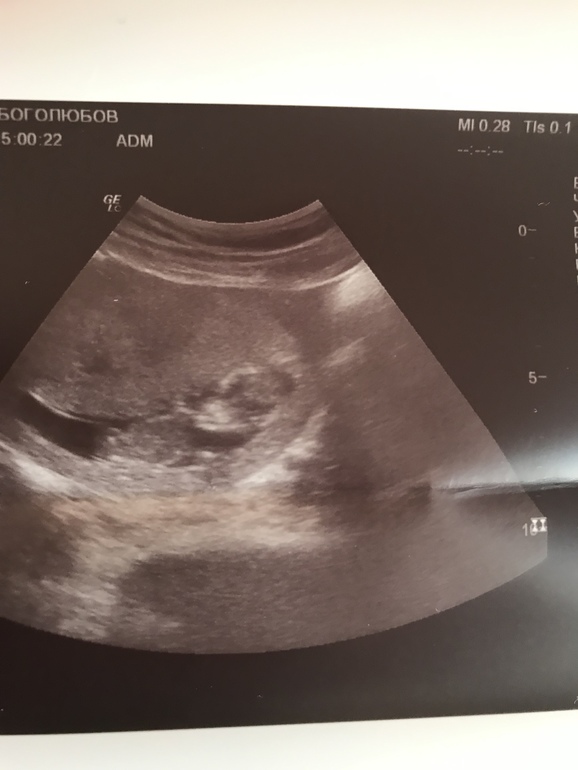

Тонус очень сильный, видно по УЗИ снимку.. Но его легко можно снять, не переживай